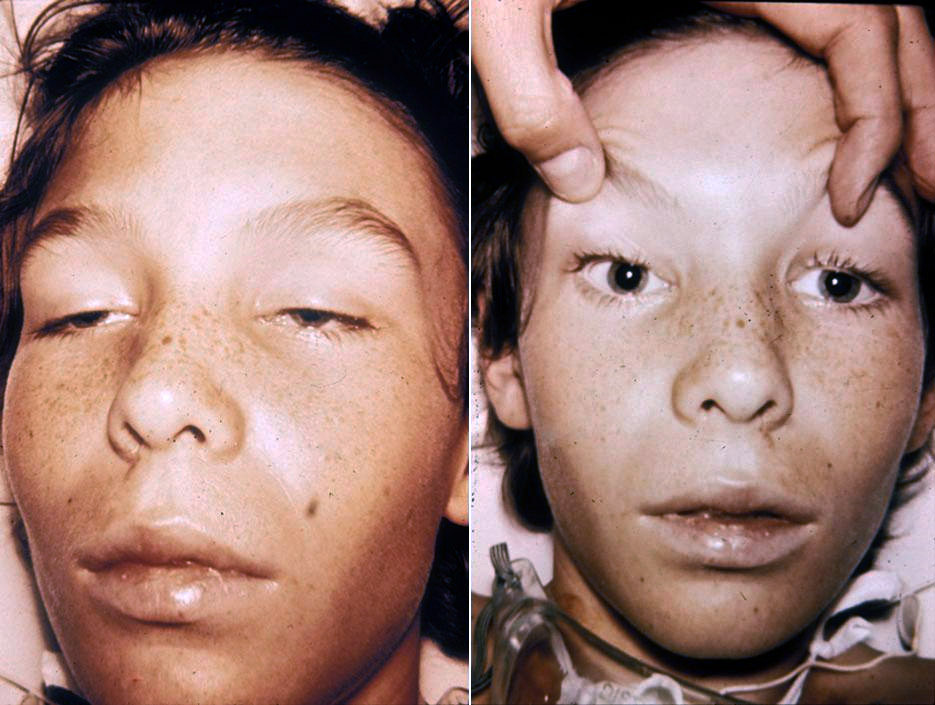

- Infant botulism can happen if the spores of the bacteria get into an infant’s intestines. The spores grow and produce the toxin which causes illness.

♦ Signs and symptoms

The disease begins with weakness, blurred vision, feeling tired, and trouble speaking. This may then be followed by weakness of the arms, chest muscles, and legs. The toxin attacks the body’s nerves and causes difficulty breathing, muscle paralysis, and even death.

Vomiting, swelling of the abdomen, and diarrhea may also occur. The disease does not usually affect consciousness or cause a fever.

Infant botulism typically has no long-term side effects but can be complicated by treatment associated adverse events. The case fatility rate is less than 1% for hospitalized babies.

infant botulism: https://www.tamingthesru.com/blog/annals-of-b-pod/b-pod-cases/infantile-botulism